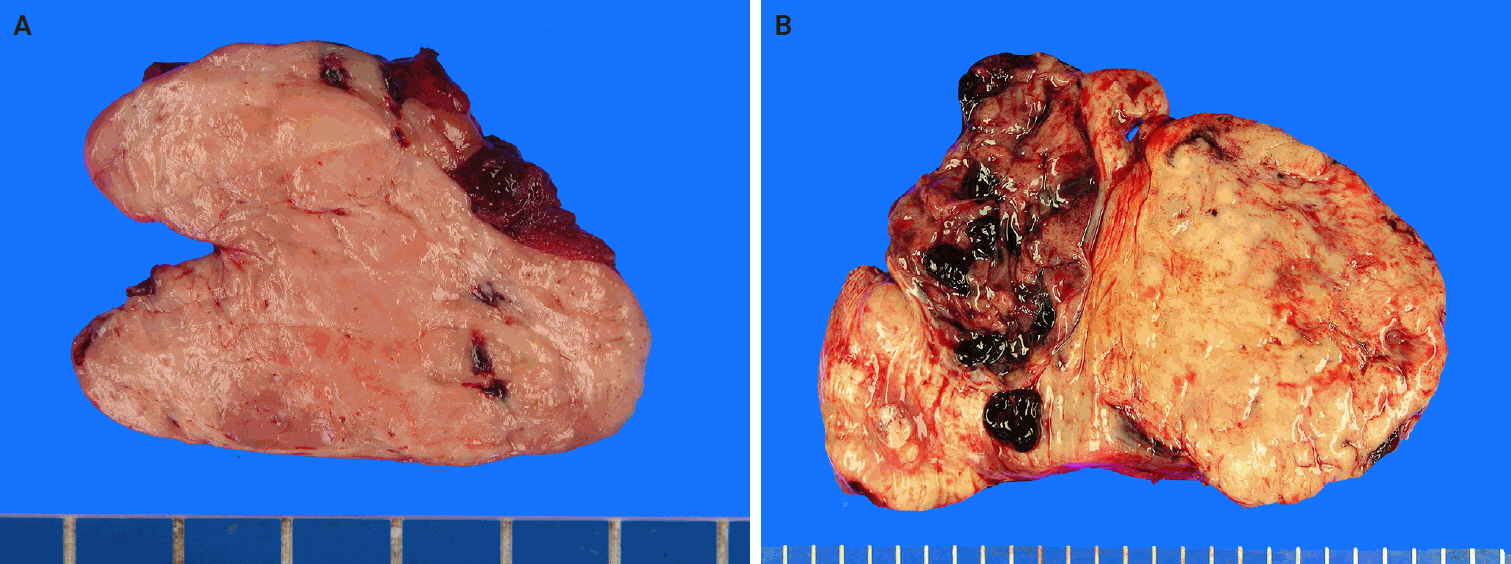

Upon imaging, SFTs typically show nonspecific radiographic features [60,61], whereas computed tomography (CT) usually yields a well-defined, occasionally lobulated, isodense mass relative to the skeletal muscle (Fig. 1). They exhibit heterogeneous contrast enhancement because of their rich vascularity [62,63]. Magnetic resonance imaging (MRI) typically shows intermediate T1 signal intensity and variable T2 signals, which correspond to fibrous (low T2) and cellular or myxoid (high T2) components [63-65]. Larger or more aggressive tumors may display heterogeneity because of fibrosis, necrosis, hemorrhage, or cystic changes [63].

Fig. 1.

Radiological findings of solitary fibrous tumor. Axial contrast-enhanced abdominal computed tomography demonstrates a large central abdominal mass. Prominent feeding vessels (arrow) are visible along the anterior aspect of the lesion.

Fig. 2.

Macroscopic findings of solitary fibrous tumor. (A) The cut surface of the tumor is well-circumscribed, with a pinkish-gray, fleshy, and solid appearance. (B) The tumor is multilobulated, with yellow-tan to gray coloration and prominent areas of hemorrhage.